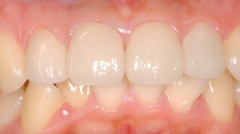

審美的治療の実例

出っ 歯が気になって来院した患者様です。海外に行くことが決まっていたので、矯正治療をするだけの時間の余裕がありませんでした。そこで、上の前歯4本をオー ルセラミッククラウンに変えました。いかがですか?どれが人口の歯か見分けがつきません。患者様ご本人も大満足してくださいました。

当院では咬み合わせ、歯列のみならず、歯肉との調和も考慮し治療にあたります。自然さを追求し、治療した後も結果を長く安定させるように、しっかりとメインテナンスサポート致します。

| Before | After |